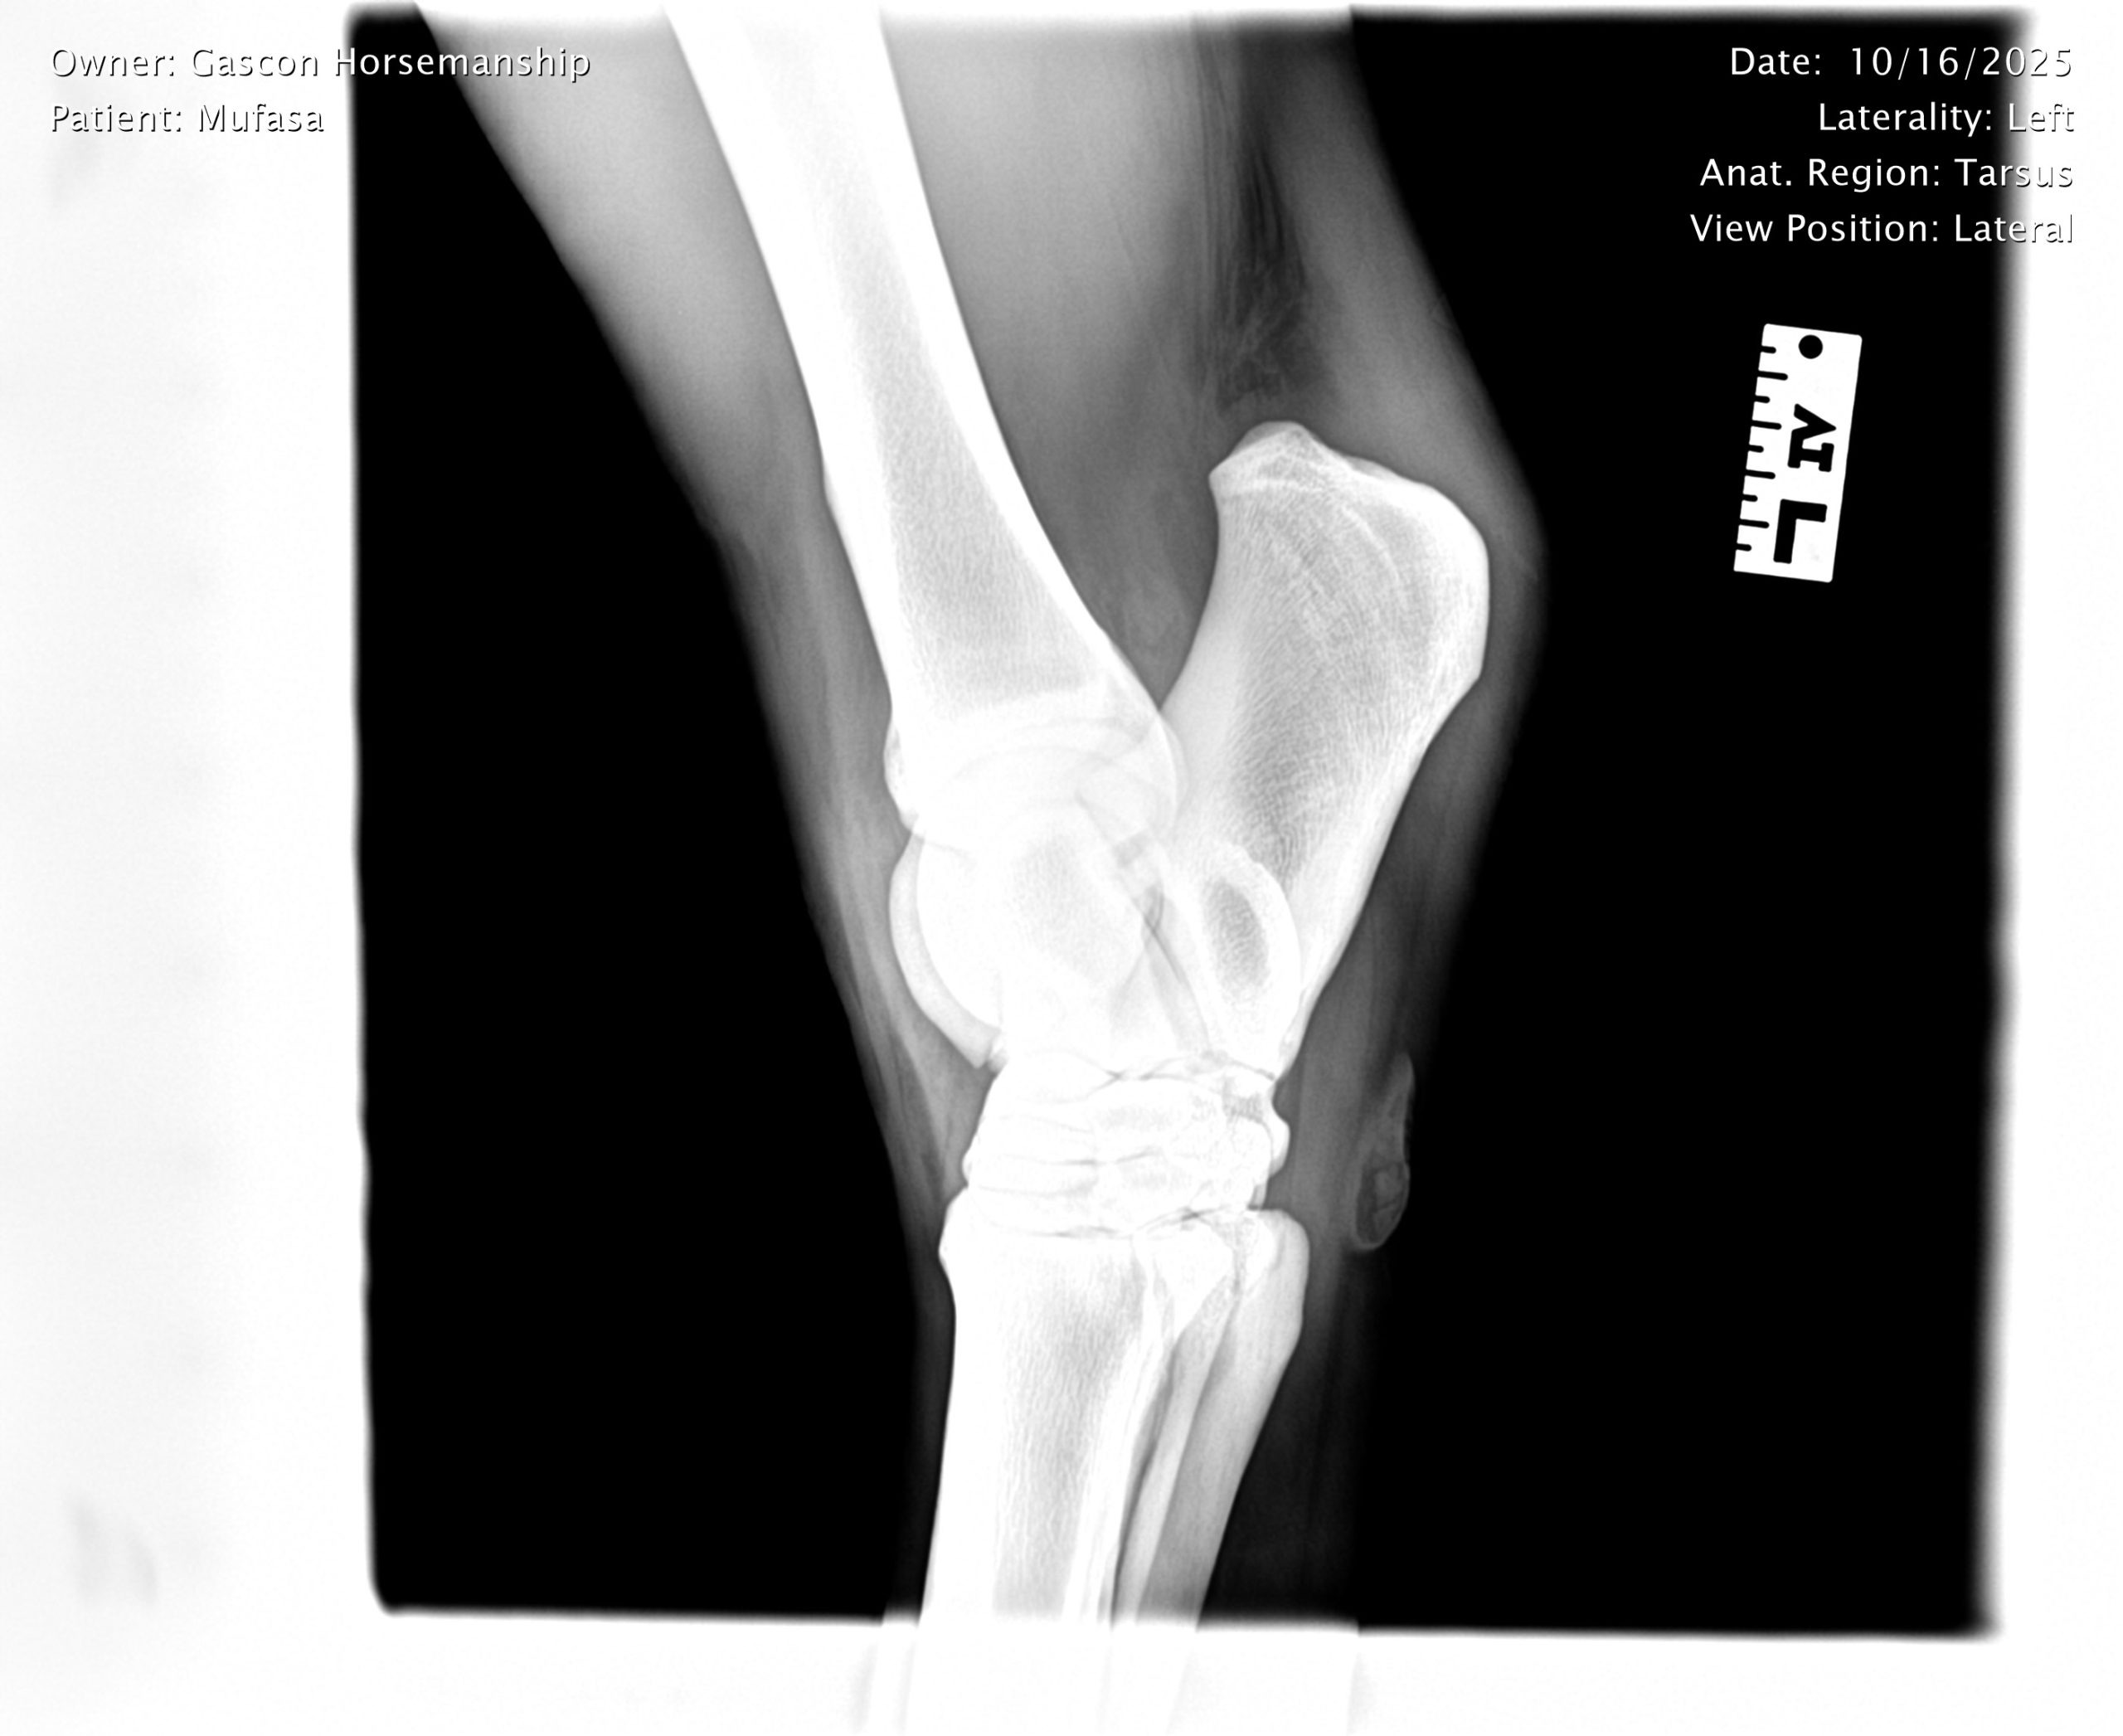

He already has a full pre-purchase exam on file, complete with 25 X-rays included in his album.